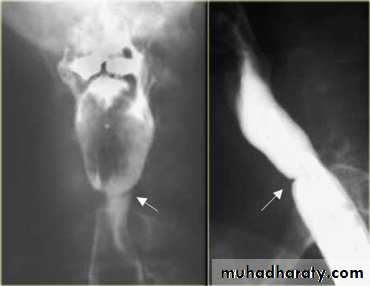

LEFT: Dilated esophagus (arrows) appears as long, well-defined structure paralleling heart RIGHT: Dilated esophagus usually deviates to right. Narrowing (arrow) at hiatus.

LEFT: CT shows dilated esophagus (arrow) that led to esophagram.RIGHT: Esophagram shows narrowing (arrow) at level of hiatus.